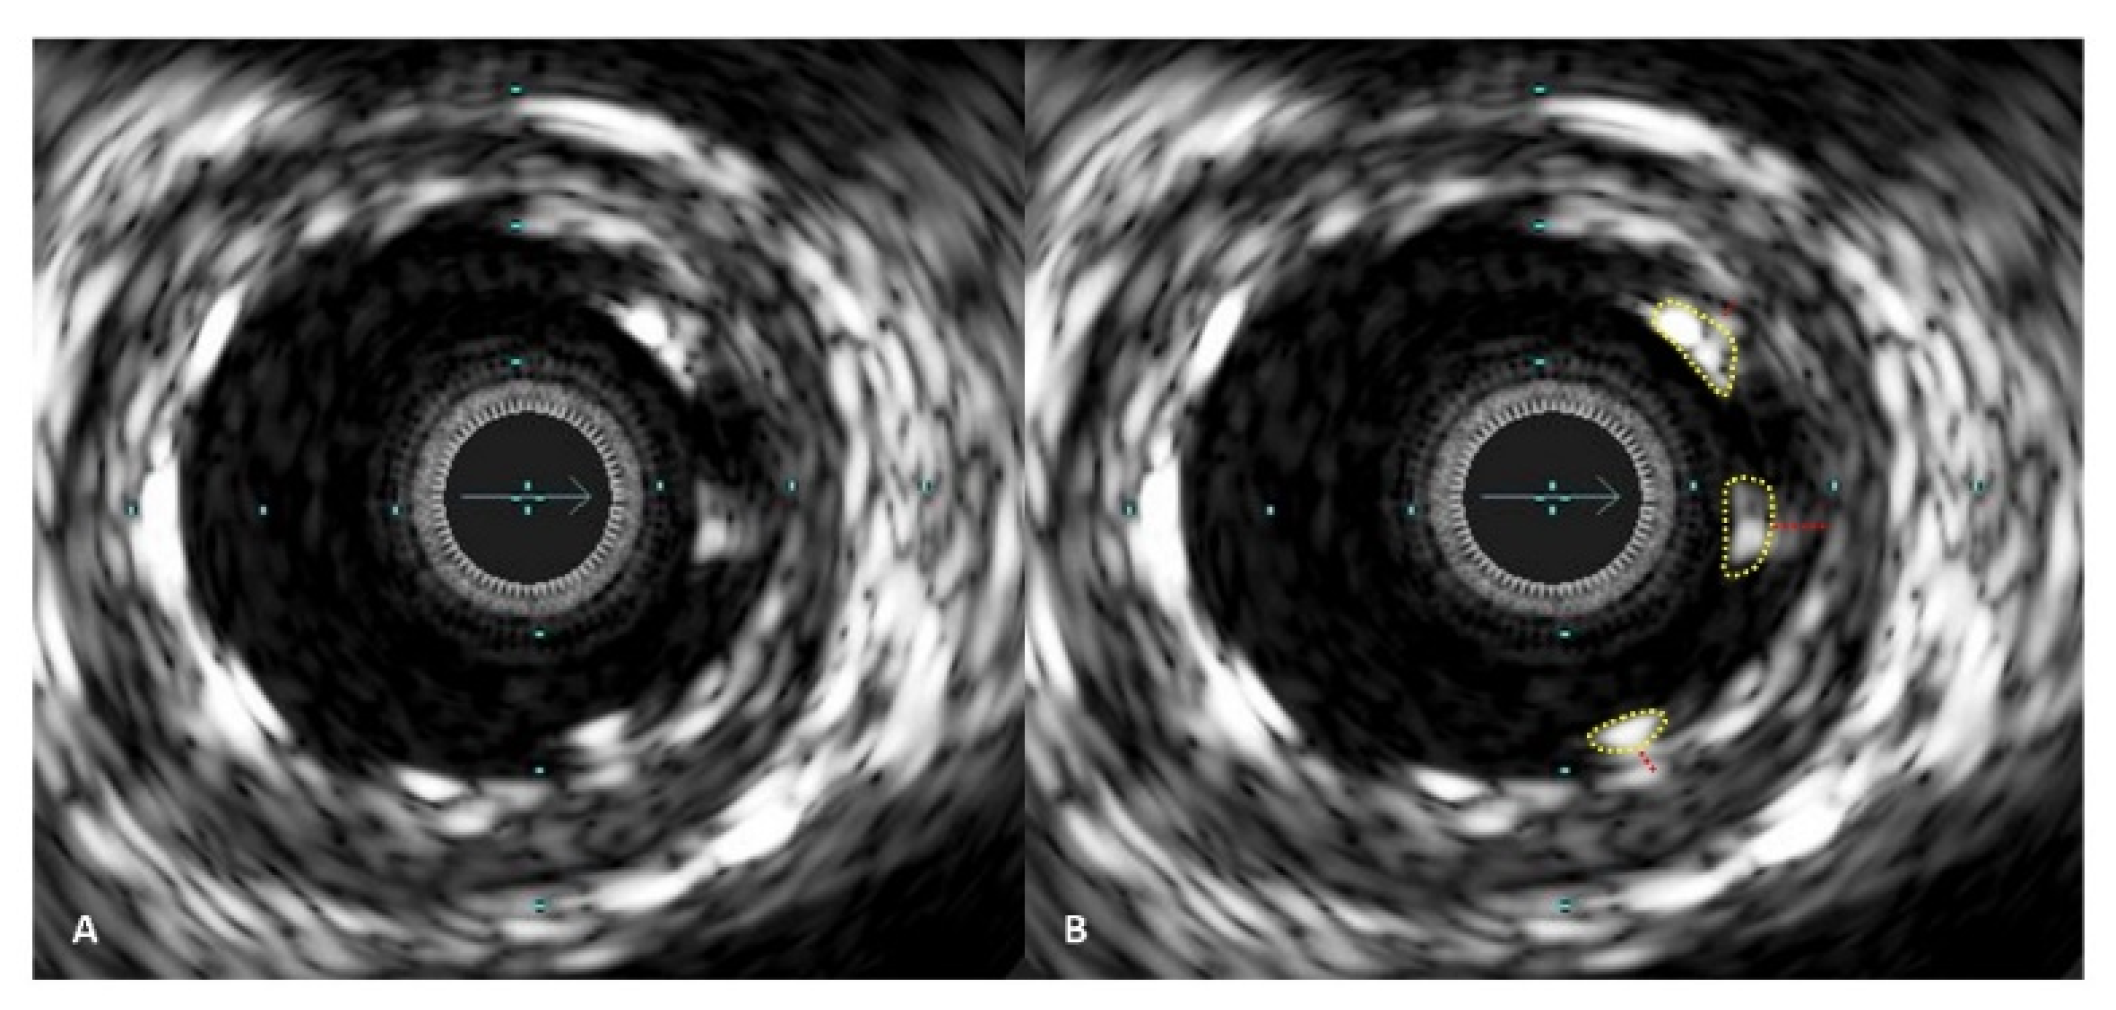

Figure 4.

IVUS images demonstrating stent malapposition. In picture (A), malapposed stent struts are visible on one side of the artery. In picture (B), the malapposed stent struts are marked with a yellow line, and the red lines indicate the distance between the stent struts and the vessel wall inner layer.